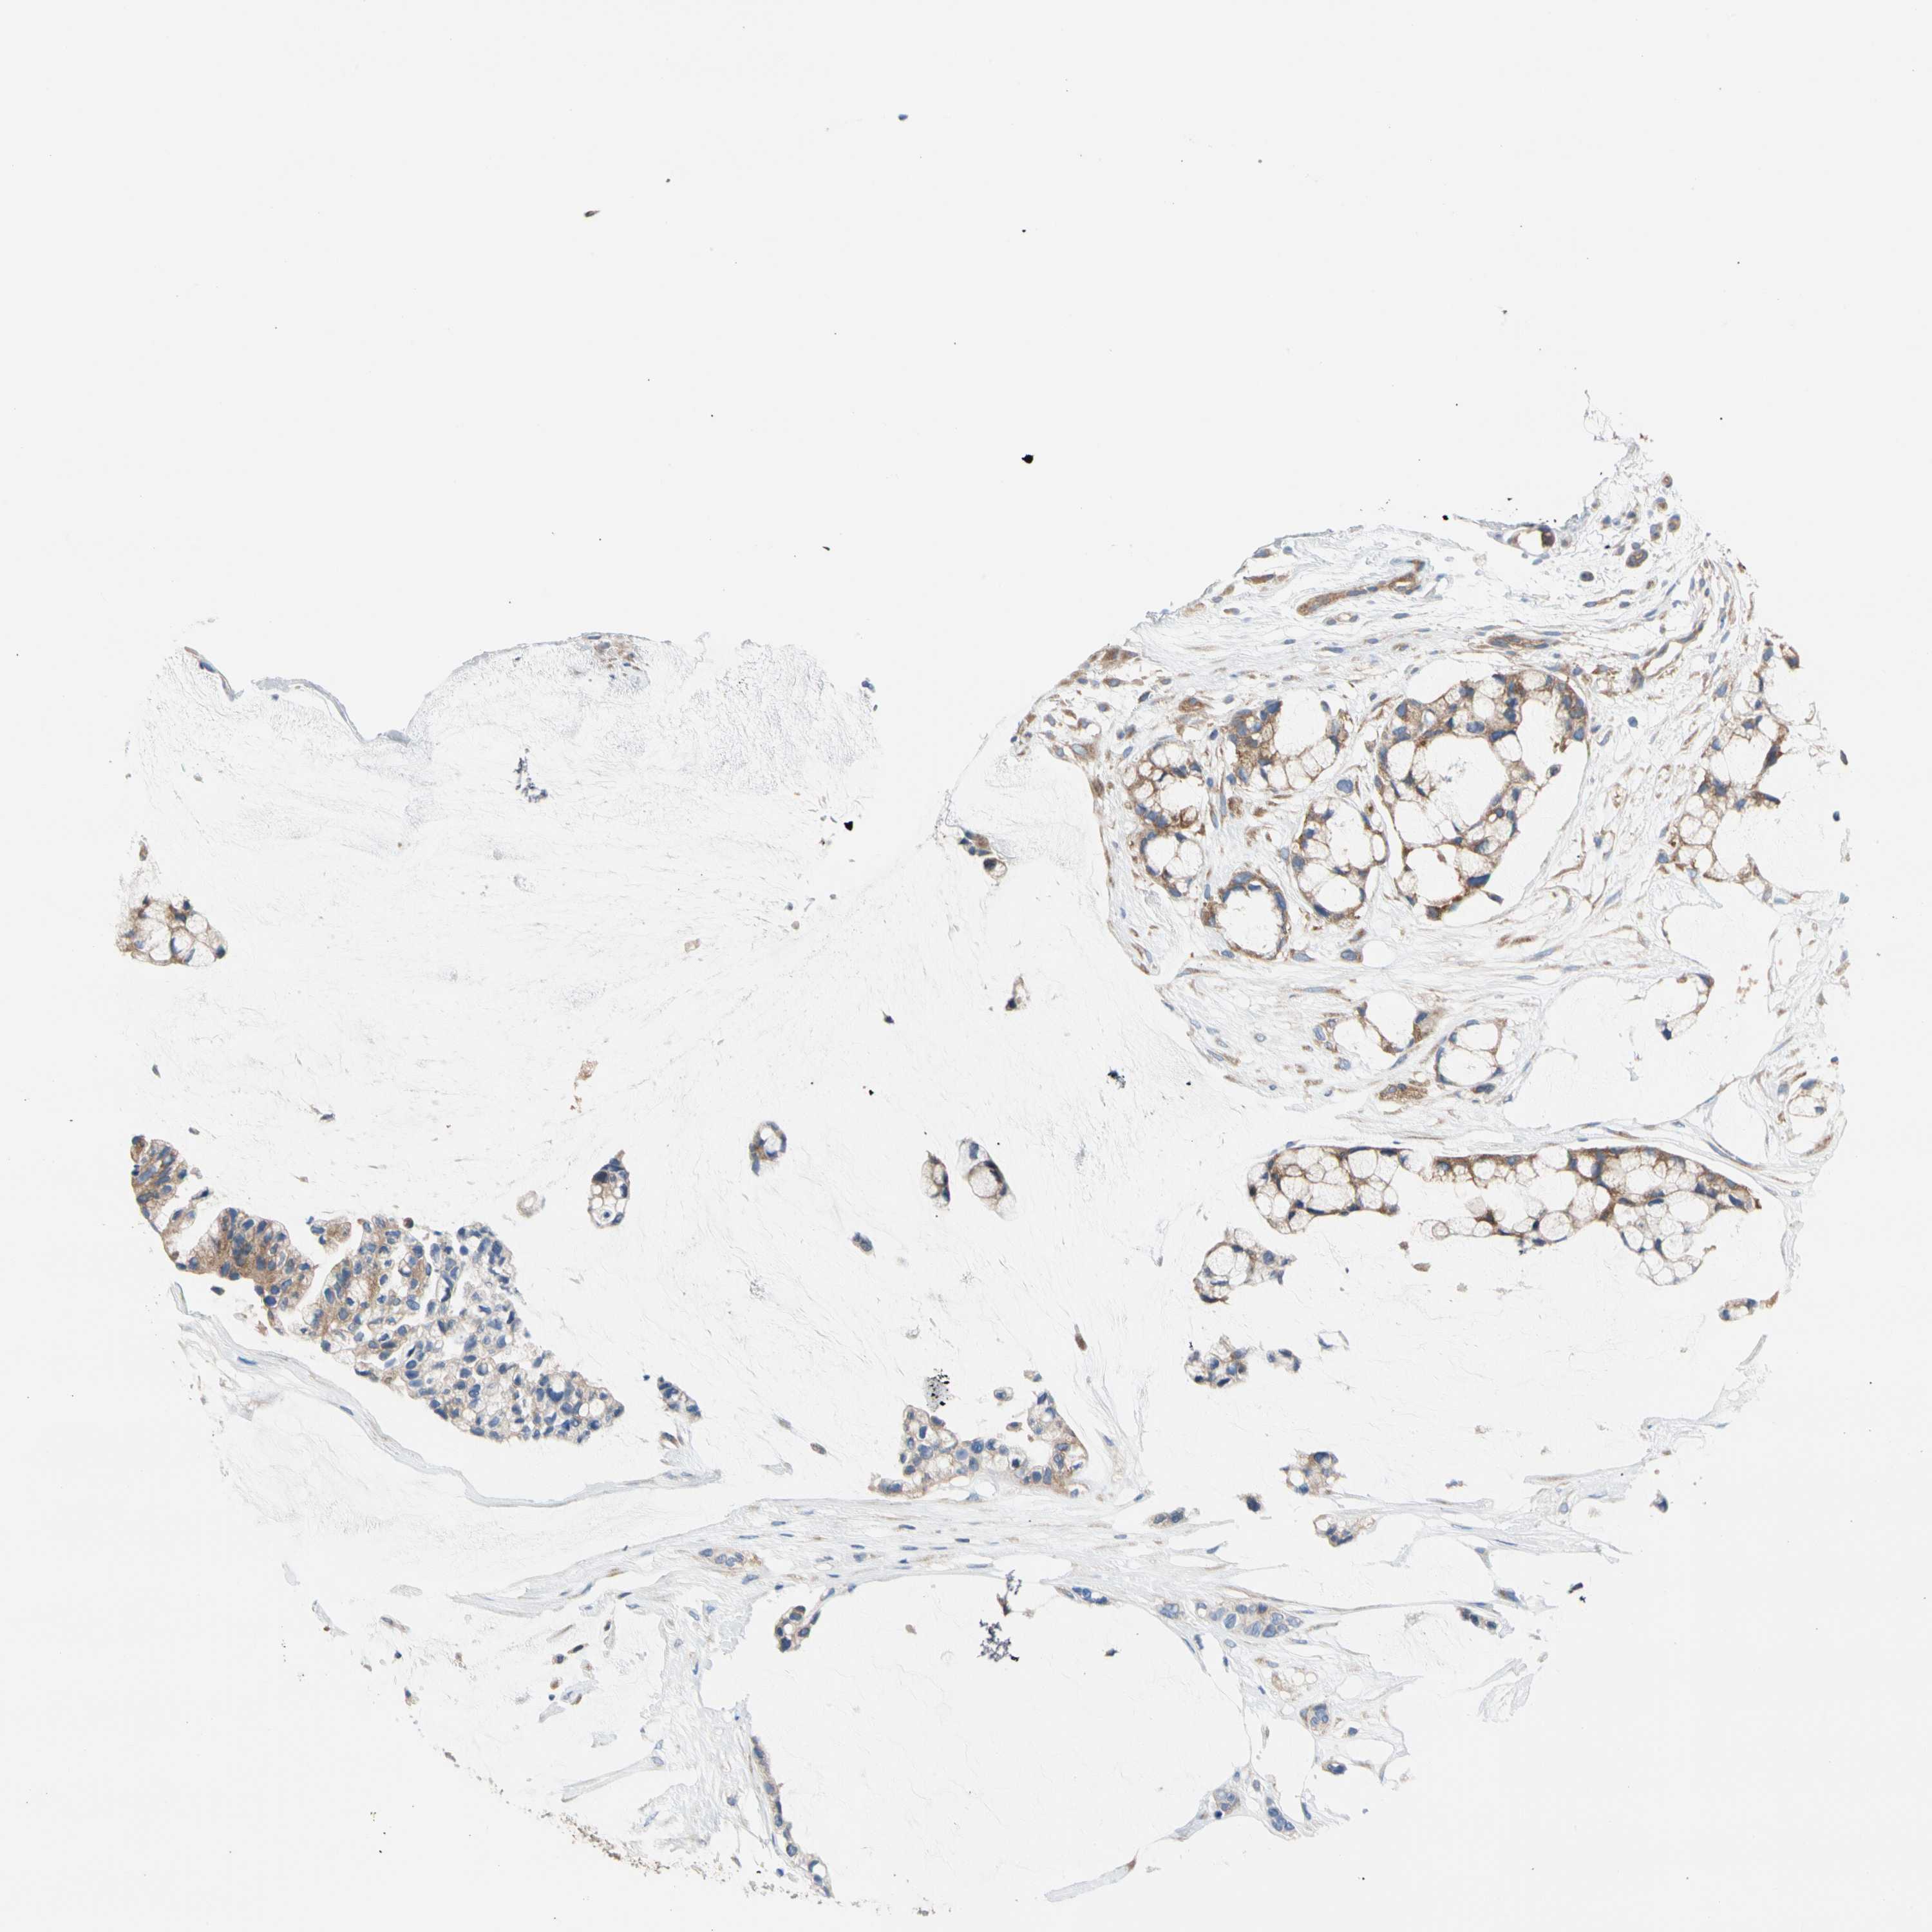

OVARIAN CANCER - Protein expressioni

A mouse-over function shows sample information and annotation data. Click on an image to view it in a full screen mode. Samples can be filtered based on level of antibody staining by selecting one or several of the following categories: high, medium, low and not detected. The assay and annotation is described here.

Note that samples used for immunohistochemistry by the Human Protein Atlas do not correspond to samples in the TCGA dataset.

Antibody stainingi

Antibody staining in the annotated cell types in the current human tissue is reported as not detected, low, medium, or high, based on conventional immunohistochemistry profiling in selected tissues. This score is based on the combination of the staining intensity and fraction of stained cells.

Each image is clickable and will lead to virtual microscopy that enables deeper exploration of all samples and also displays staining intensity scores, fraction scores and subcellular localization as well as patient and tissue information for each sample.

Antibody HPA003116

Antibody HPA024694

Antibody CAB004419

Cystadenocarcinoma, mucinous, NOS

Carcinoma, endometroid

Cystadenocarcinoma, serous, NOS

Carcinoma, NOS